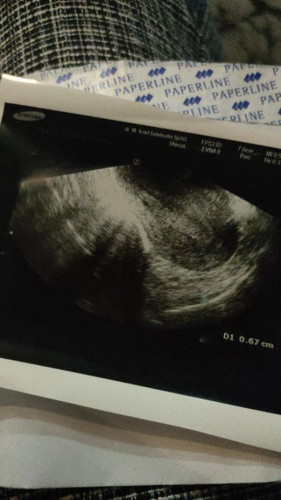

Assalamualaikum bunda2 , di postingan saya sebelumnya saya makasih byk atas segala doa2 nya , mudah2an doa2 baik jg terkabul untuk bunda semua. Dan terimakasih semangat nya , saya insyaAllah ikhlas.🤍 Kemarin malam saya kontrol dokter , sudah usg dan ternyata di rahim masih banyak sekali jaringan2 yg belum keluar , rahim belum bersih. Dokter mengharuskan kuret , tapi saya gamau karena takut😐 Jadi saya diksh obat peluruh , dan diksh waktu 1 minggu , minggu depan kontrol kalau masih blm bersih harus kuret hari itu juga. Bunda2 ada tips ga biar bersih rahim nyaa , saya tkt bgt kuret karena pas keguguran kmren di bidan miss v saya di ubek2 gt nyilu bgt sakit😭 pas HSG juga saya sakit bgt 2 hari gabisa jalan. Apalagi kuret , saya takut😭😭😭 Gumpalan2 nya kluar masih sedikit2 bund pdhal kata dokter msh banyak di rahim😥 hanya diksh obat peluruh buat 4 butir (1hari 2x). Mohon tips nya bunda kalau yg udh pengalaman🙏 sekali lagi terimakasih bunda2🤍 #bantusharing #pleasehelp #keguguran